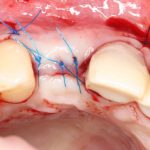

Вот клиническая картина через 4 месяца после ранее проведенной имплантации с остеопластикой:

Как видишь, коллеги из недалекой дружественной страны не осилили снятие швов. Мне это не нравится, хотя и объясняет, почему люди готовы ехать за тыщи километров ради 20-минутной операции удаления зуба мудрости.

Ну хорошо. Швы сняли. Делаем разрез. Обрати внимание, что после всех проведенных операций у нас остается очень небольшой по ширине слой жевательной слизистой оболочки:

Устанавливаем формирователи десневой манжеты. Сегодня я называю эту процедуру не менее важной, чем любой другой этап имплантологического лечения:

И швы. Просто швы. Никаких дополнительных процедур.

Если честно, то сейчас бы я использовал другой шовный материал и другой тип швов. Одно неизменно, — и я об этом много раз говорил, — самая широкая часть формирователя десны должна находиться на уровне десны. Так, чтобы эффективно отрабатывать т. н. «биологическую ширину».